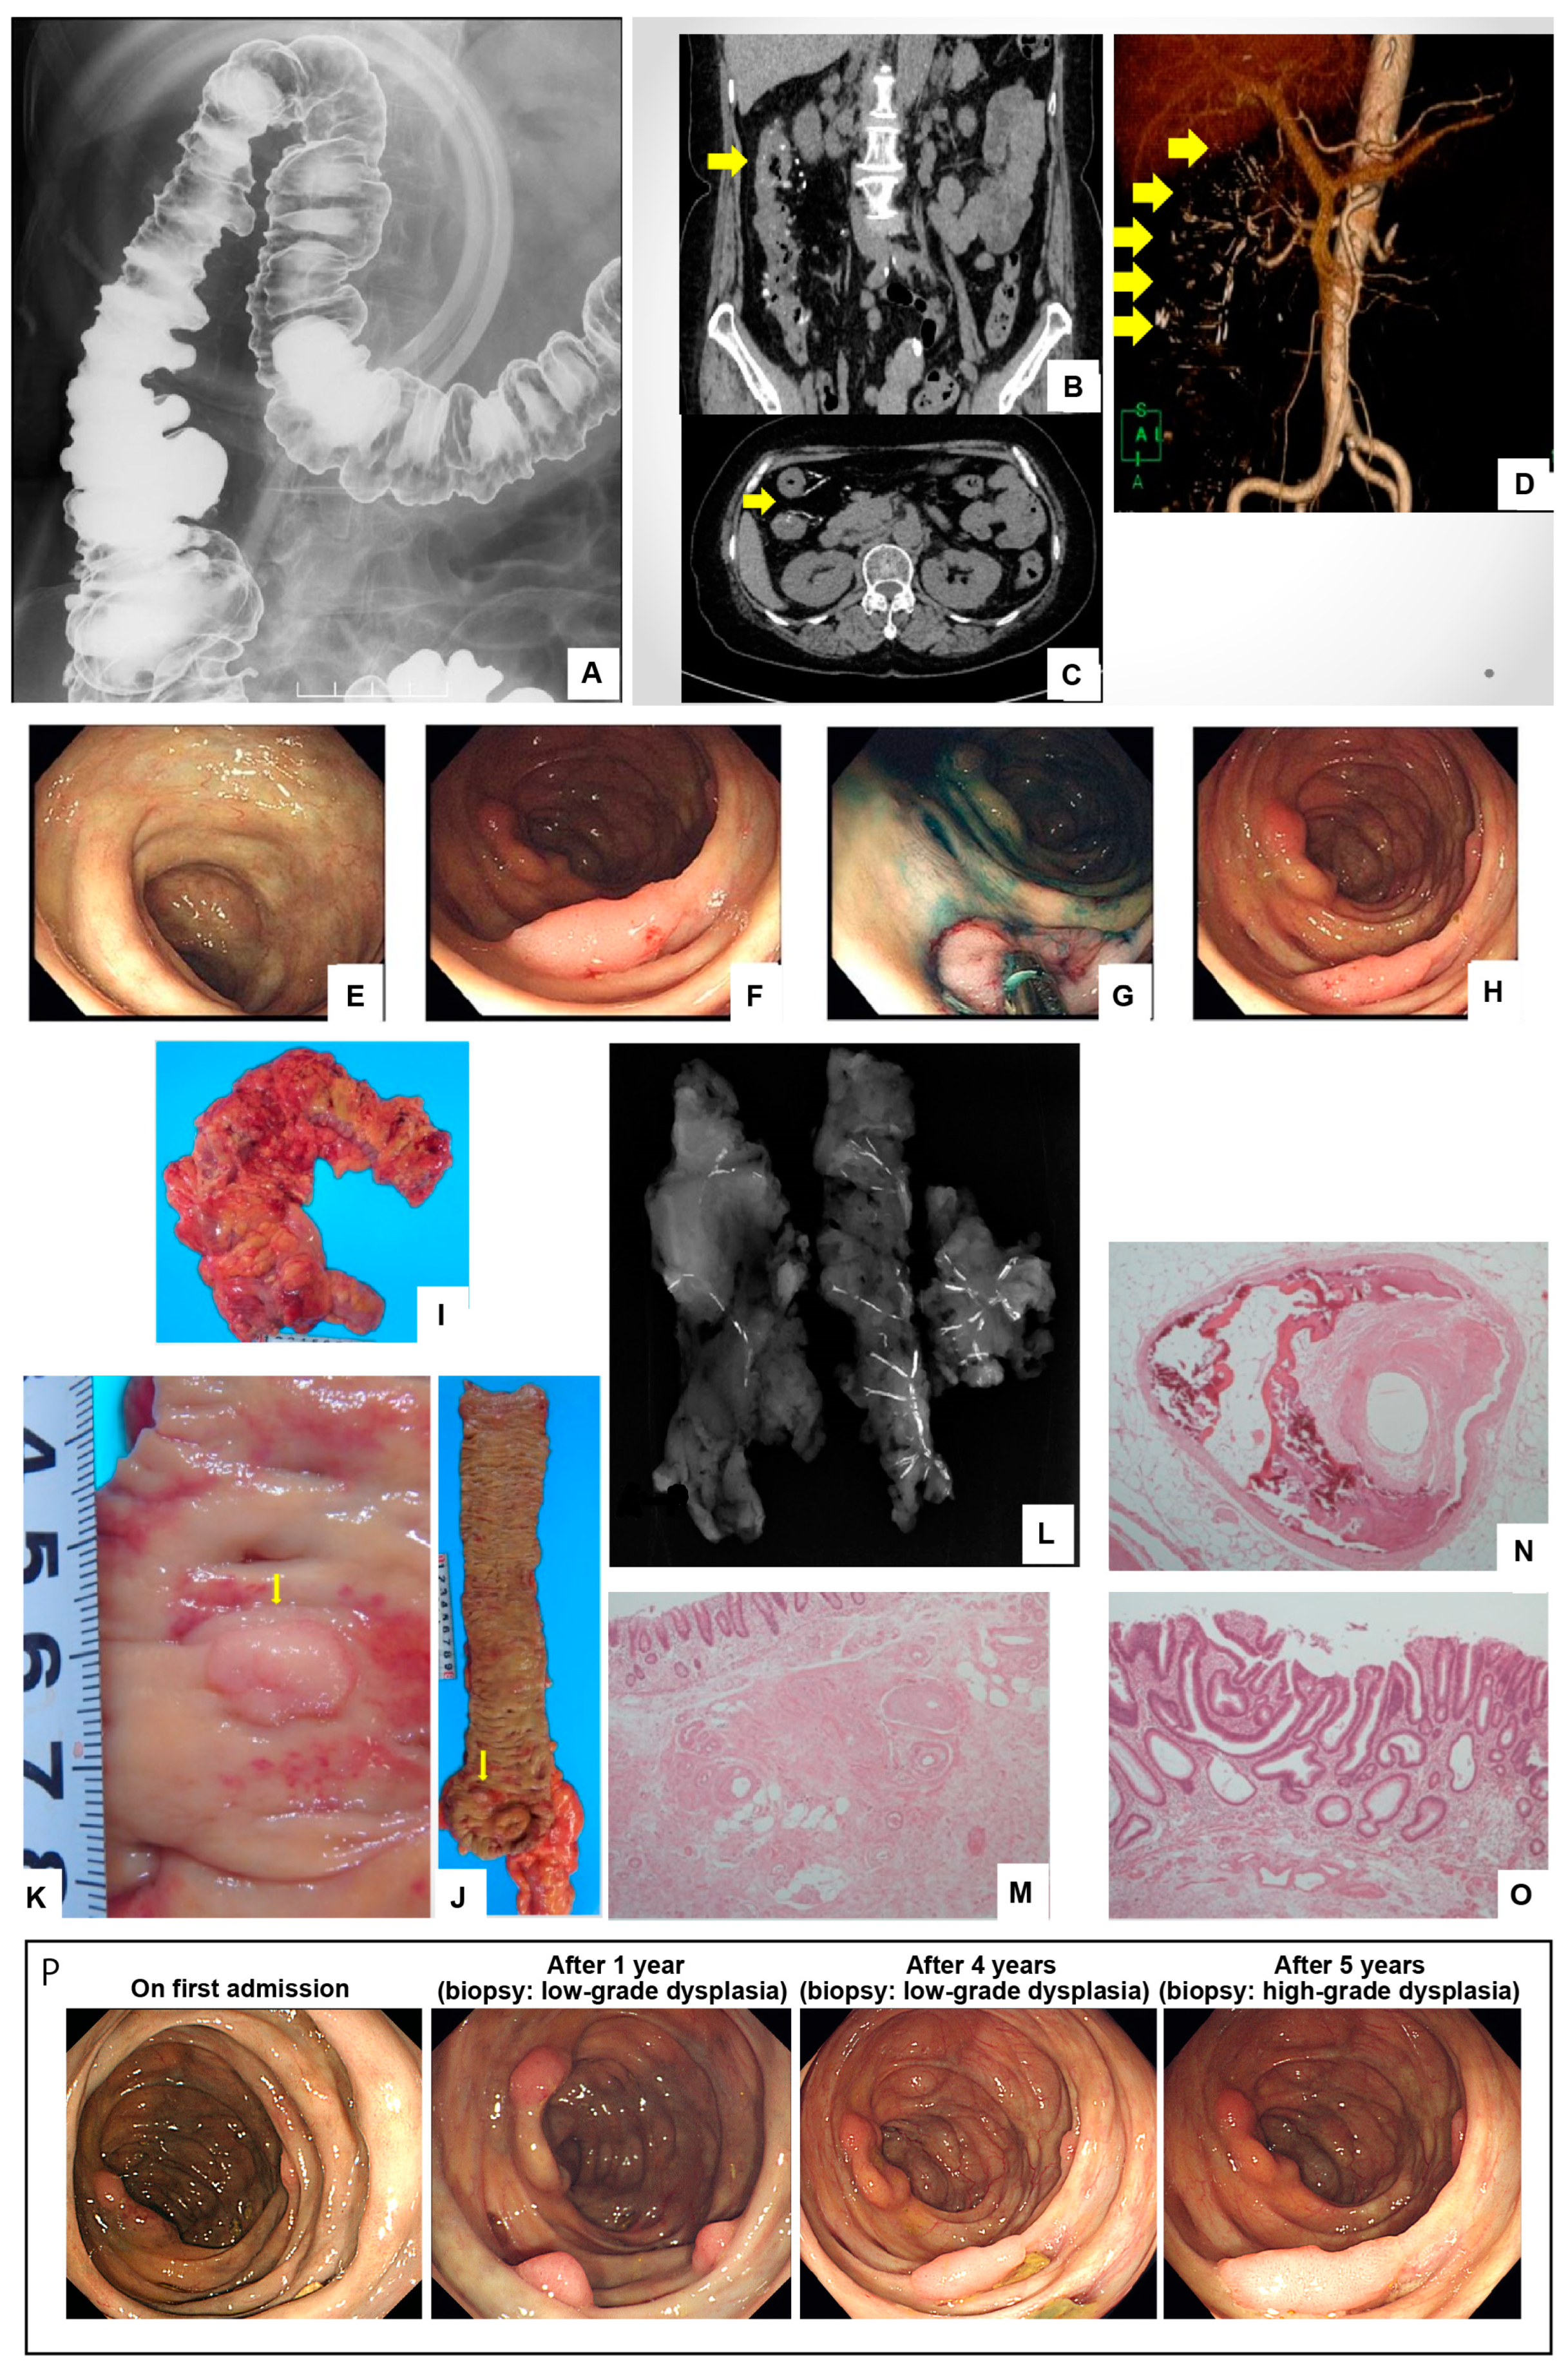

Hangeshashinto-Associated Mesenteric Phlebosclerosis and Highly Atypical Adenoma Requiring Laparoscopic Right Hemicolectomy

Nishiwaki, R.; Inoue, Y.; Sugao, M.; Sugimasa, N.; Hamaguchi, T.; Noji, M.; Takeuchi, K.; Ito, Y.; Kato, T.; Yasuma, T.; et al. Hangeshashinto-Associated Mesenteric Phlebosclerosis and Highly Atypical Adenoma Requiring Laparoscopic Right Hemicolectomy. Diagnostics 2024, 14, 565. https://doi.org/10.3390/diagnostics14050565